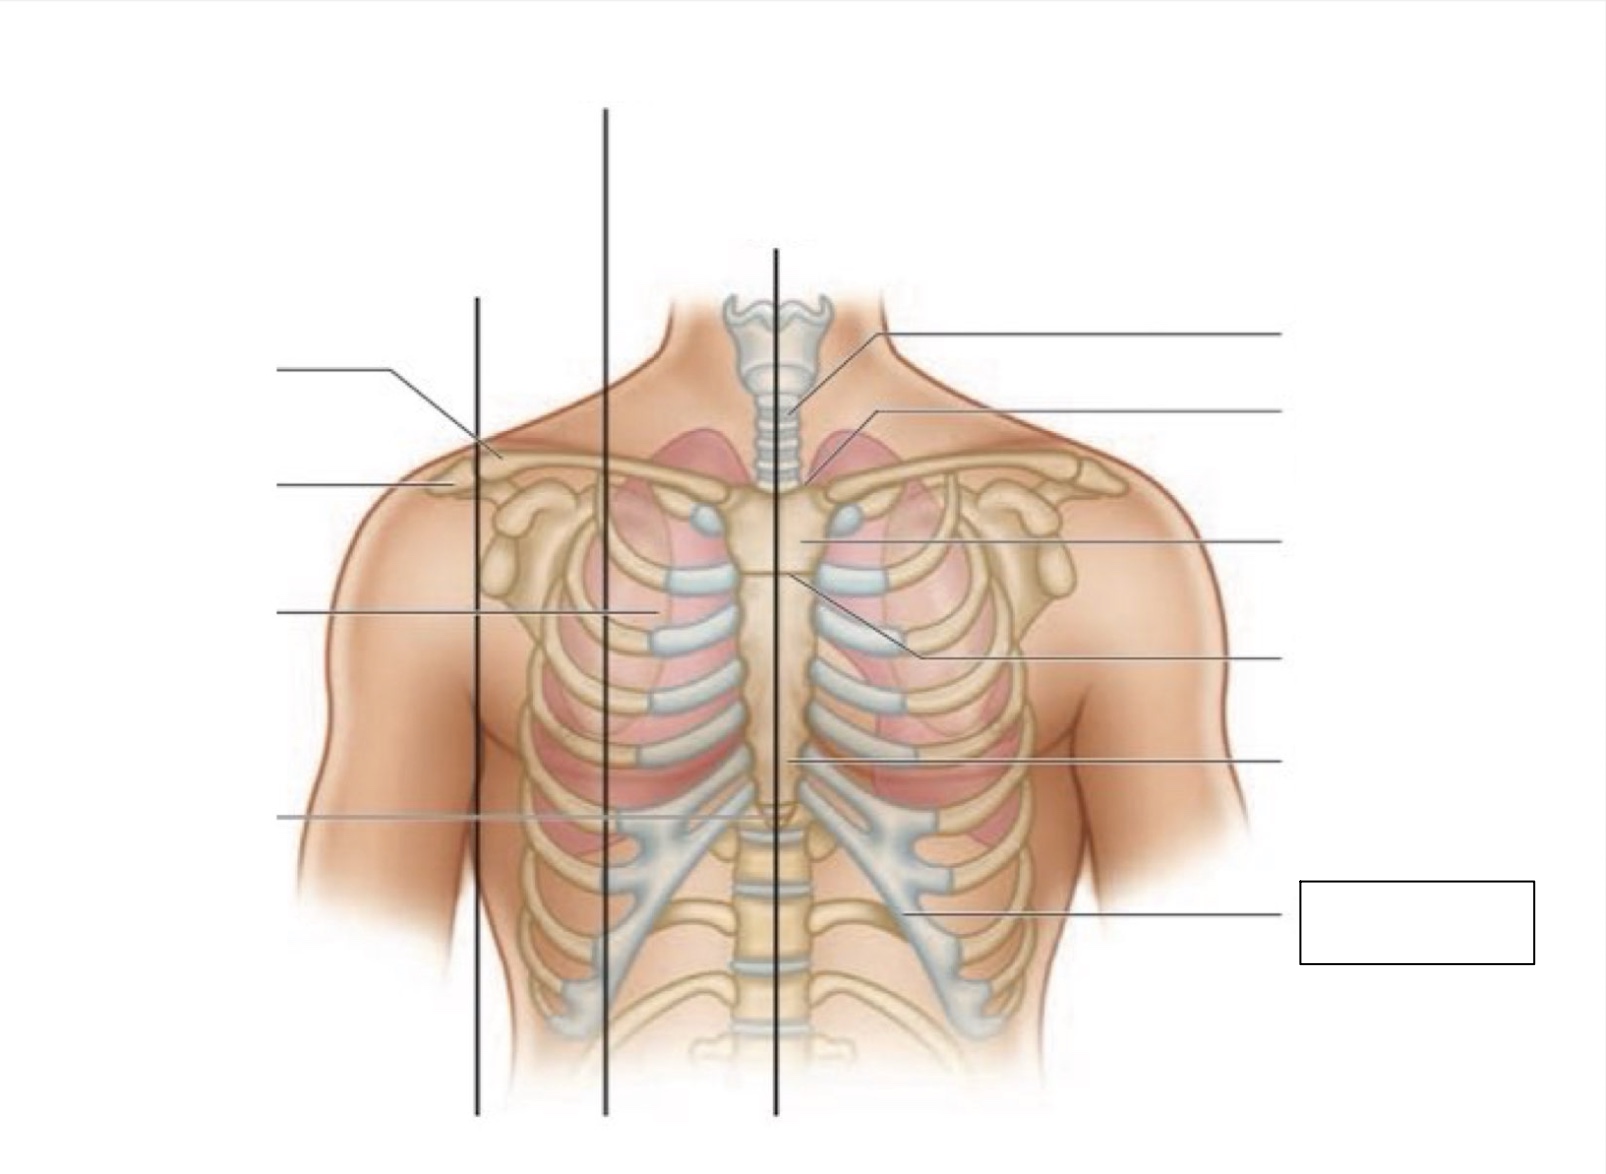

inferior angle of scapula

scapula

midscapular line

midspinal line

spinous process